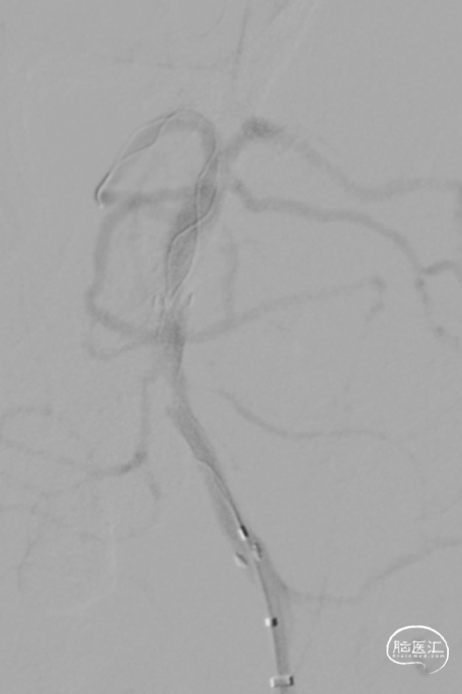

微导丝微导管通过闭塞段,在右侧大脑后动脉手推造影证实真腔,明确闭塞段,可见造影剂返流至基底动脉尖部,且证明闭塞确为支架内再狭窄导致闭塞。

释放加奇4.0mm*30mm Syphonet®取栓支架,可见支架通体显影。